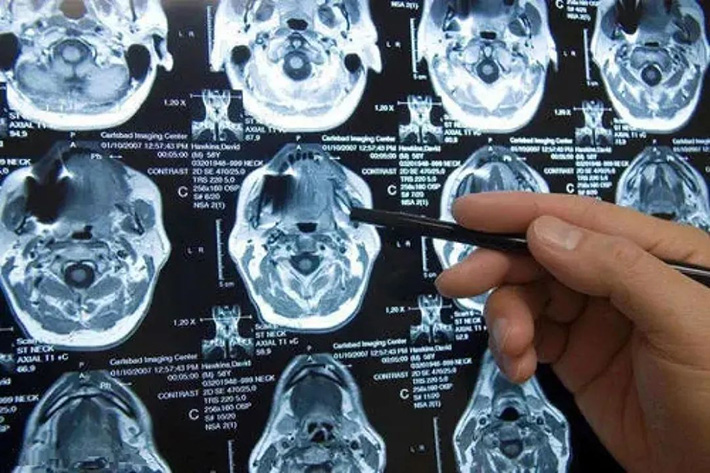

Las imágenes por resonancia magnética también se denominan imágenes por espín, también conocidas como imágenes por resonancia magnética, que es la traducción del inglés Magnetic Resonance Imaging, conocida como MRI. La resonancia magnética es desde el nivel atómico, a través del campo magnético de gradiente externo para detectar sus cambios físicos y dibujar la imagen de la estructura interna del objeto. Es un proceso muy complicado, y no es tan profundo como una ciencia popular.

En circunstancias normales, la dirección de las líneas de fuerza magnética de cada molécula de agua es aleatoria. Bajo la acción de un fuerte campo magnético de resonancia magnética nuclear, las líneas de campo magnético de estas moléculas de agua mostrarán consistencia. Cuando el campo magnético desaparezca, las líneas de fuerza magnética de estas moléculas de agua volverán a ser aleatorias. estado. La Resonancia Magnética Nuclear es para recopilar datos sobre los cambios en las líneas del campo magnético del campo magnético del cuerpo humano a través del proceso alterno de emitir un campo magnético y detener el campo magnético, y reconstruir la imagen a través de operaciones informáticas complejas.

El equipo de resonancia magnética se compone principalmente de tres componentes básicos, a saber: la parte del imán, que está compuesta por el imán principal (que genera un fuerte campo magnético estático), la bobina de compensación (bobina de corrección), la bobina de radiofrecuencia y la bobina de gradiente. ; la parte del espectrómetro de resonancia magnética, que incluye principalmente la radiofrecuencia La parte de transmisión se compone de un conjunto de sistema de recepción de señal de resonancia magnética; la parte de procesamiento de datos y reconstrucción de imágenes está compuesta por un convertidor de señales, un registro temporal, un procesador de imágenes, una consola y una pantalla.

El campo magnético que utiliza la resonancia magnética nuclear es muy fuerte, generalmente entre 1,5T y 3T. T (Tesla) es una unidad de fuerza de campo magnético muy alta del campo magnético. 1T es igual a 10000Gs (Gauss), mientras que el campo magnético terrestre es de solo 0,3Gs en el ecuador, 0,6Gs en los polos norte y sur, y el imán de rubidio más fuerte tiene una fuerza de campo magnético de solo 300Gs. Por lo tanto, la intensidad del campo magnético de la RMN es aproximadamente 50.000 veces mayor que la de la Tierra y 100 veces mayor que la del imán más fuerte.

resonancia magnética nuclear

Sensible al diagnóstico temprano, puede mostrar anomalías en las primeras etapas de algunas lesiones y puede detectar problemas antes que los métodos de TC y ultrasonido B. Es más adecuado para exámenes de la cabeza, médula espinal, huesos, extremidades, etc. Por lo tanto, es especialmente efectivo para el examen de la base del cráneo y el canal espinal. En comparación con la TC, también compensa el defecto de que no puede ser directamente una imagen multiplanar. La angiografía se puede formar sin inyección de agente de contraste, y la lesión se puede mostrar más claramente.

Desventajas: el método de imagen es complicado, el precio es relativamente más alto y generalmente no es la primera opción para el diagnóstico de enfermedades; dado que el equipo de emergencia no puede ingresar a la sala de resonancia magnética, este examen generalmente no es adecuado para pacientes particularmente críticos; La resonancia magnética no es buena para el feto, por lo que las mujeres embarazadas no pueden usarla. Esta prueba también está contraindicada en pacientes con implantes metálicos (p. ej., marcapasos, ciertos stents) en el cuerpo; La resonancia magnética muestra una calidad de imagen deficiente de las lesiones calcificadas y la piel ósea y, por lo tanto, no es adecuada para el diagnóstico por imágenes de fracturas y otras afecciones.